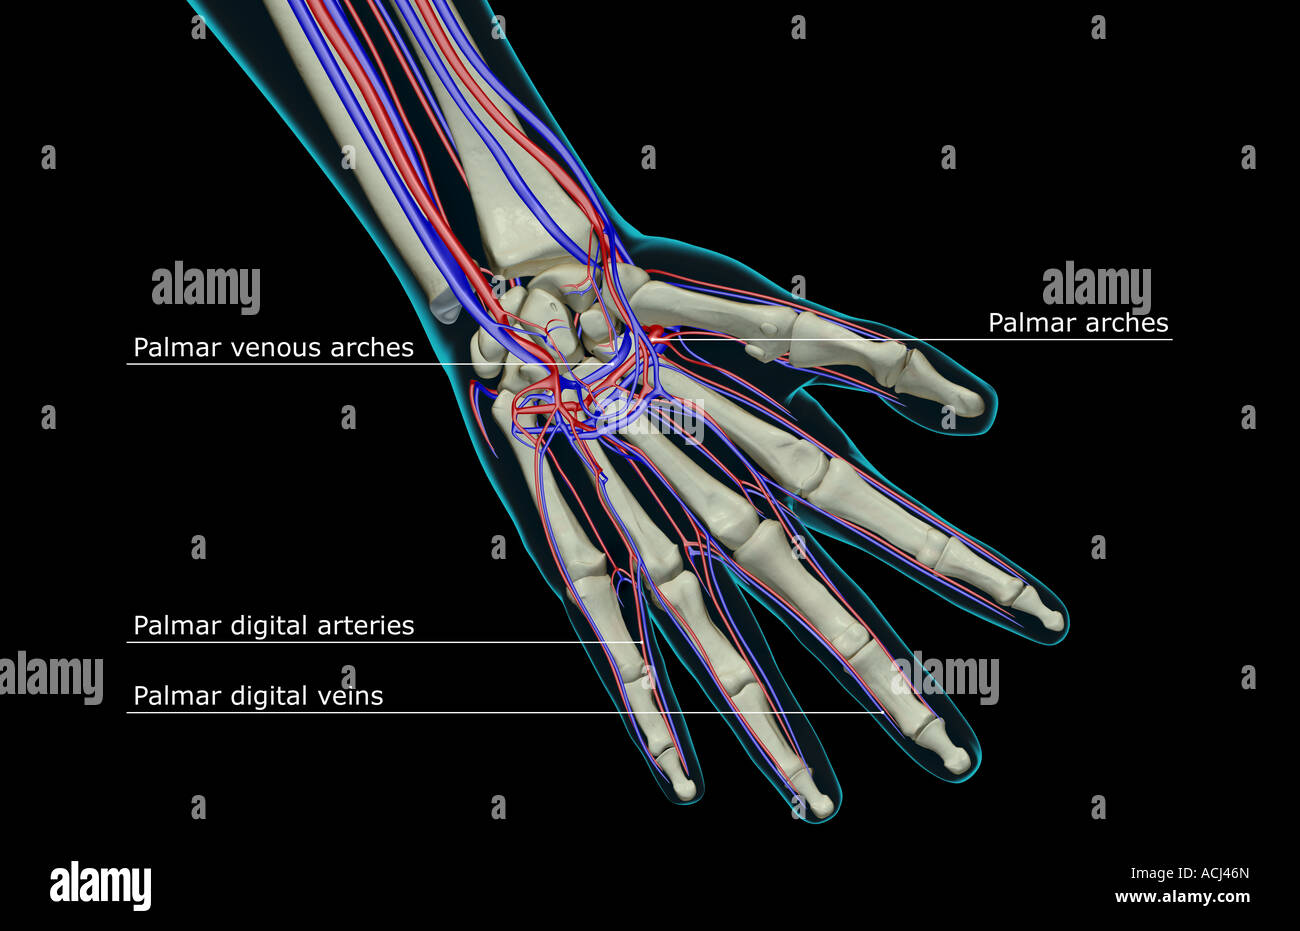

The blood supply of the hand Stock Photohttps://www.alamy.com/image-license-details/?v=1https://www.alamy.com/stock-photo-the-blood-supply-of-the-hand-13166348.html

The blood supply of the hand Stock Photohttps://www.alamy.com/image-license-details/?v=1https://www.alamy.com/stock-photo-the-blood-supply-of-the-hand-13166348.htmlRFACJ46N–The blood supply of the hand